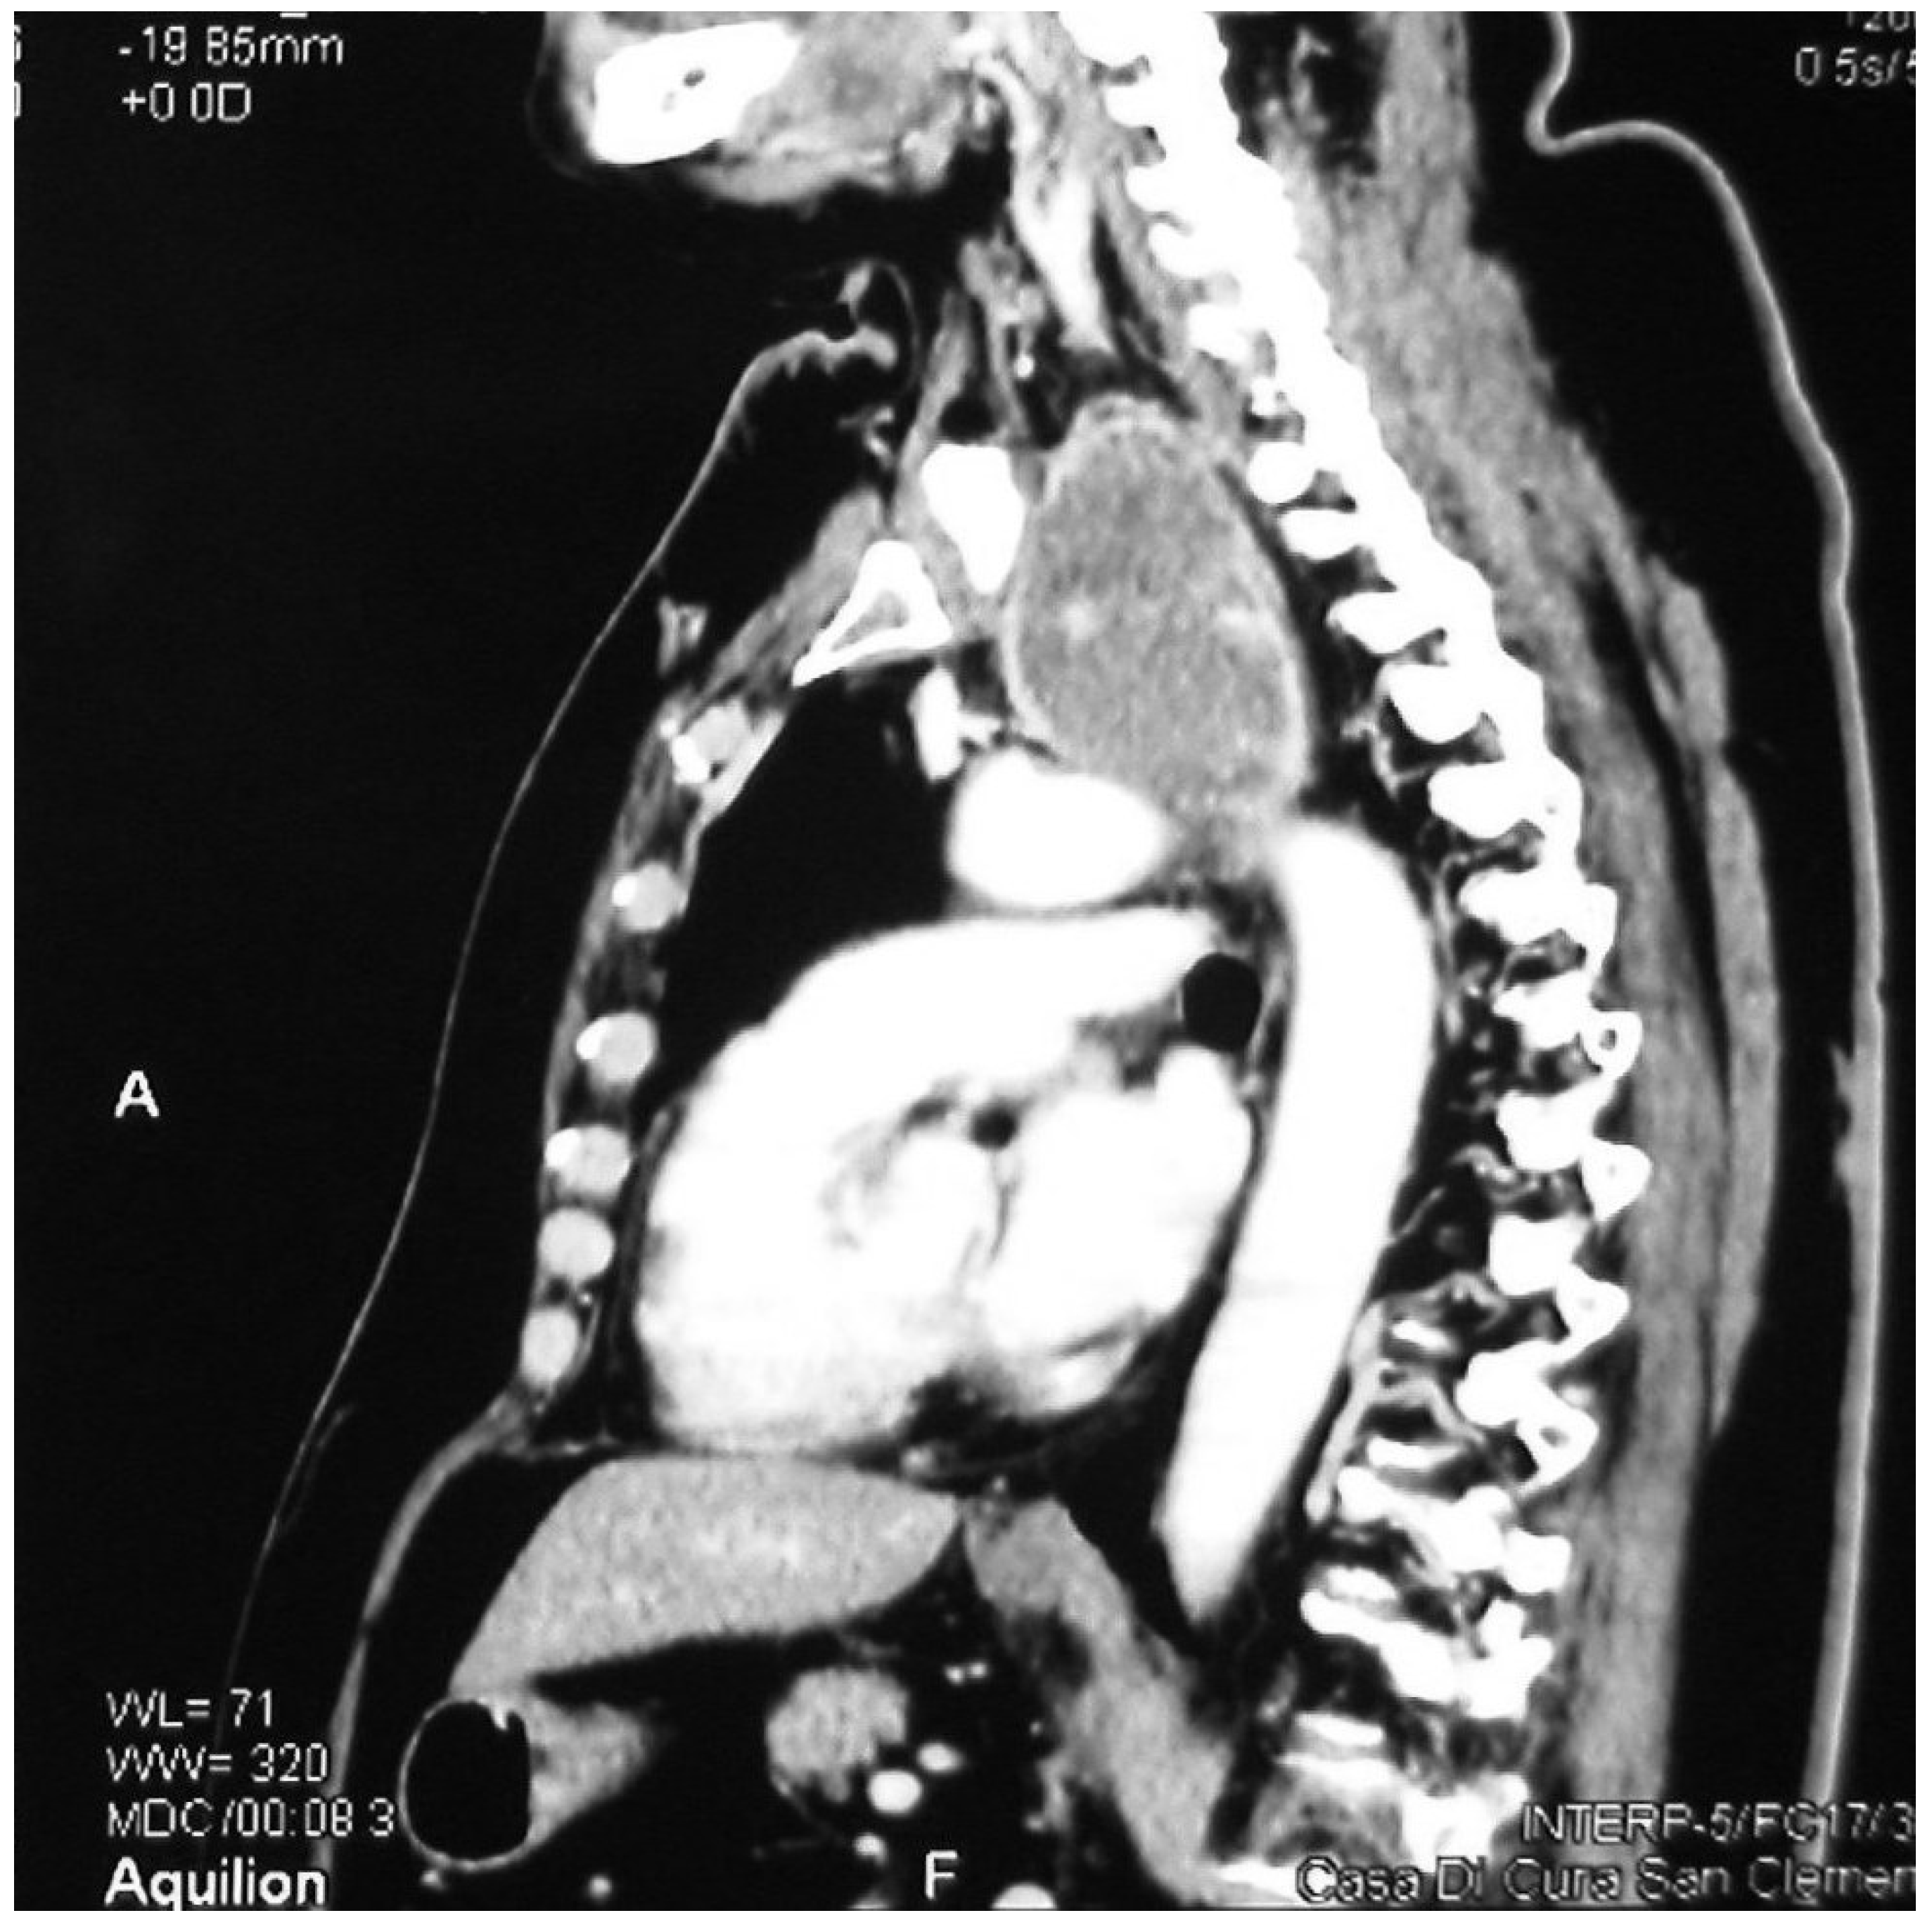

Figure 2.

Sagittal CT showing a retrovascular retrosternal goitre.